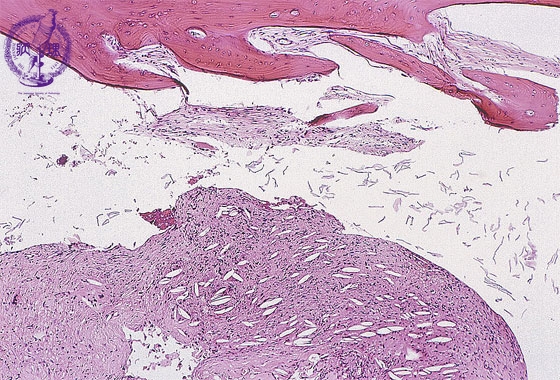

- (1)cholesteatoma, otitis media

Bone fragments and fibrous granulation tissues are seen. Cholesterol clefts are also seen in the granulation tissue (arrow).